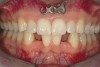

Fig 4. Note gingival inflammation caused by biologic width violation. Provisional restorations were placed on Nos. 6, 8, 9, and 11, and corticotomies were performed from Nos. 3 to 14.

Figure 4

Fig 5. One week postsurgery with mesial buildups on Nos. 5 and 12 and thin pontics on archwire to conceal spaces during closure.

Figure 5